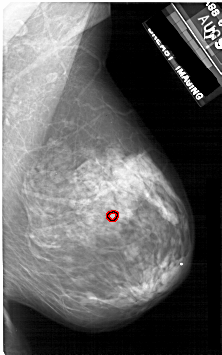

A_1924_1.RIGHT_MLO

RIGHT_MLO LINES 5311 PIXELS_PER_LINE 3316 BITS_PER_PIXEL 12 RESOLUTION 43.5 OVERLAY

FILE: A_1924_1.RIGHT_MLO.OVERLAY

TOTAL_ABNORMALITIES 1

ABNORMALITY 1

LESION_TYPE CALCIFICATION TYPE PLEOMORPHIC DISTRIBUTION CLUSTERED

ASSESSMENT 4

SUBTLETY 4

PATHOLOGY BENIGN

TOTAL_OUTLINES 1

BOUNDARY